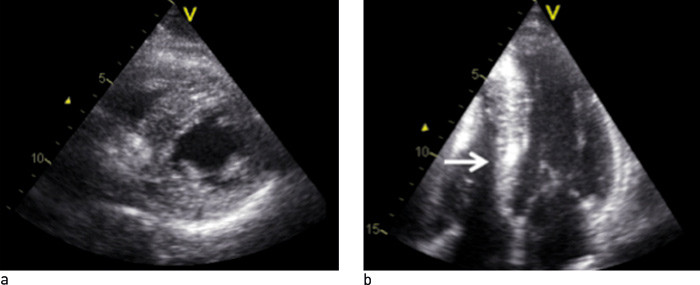

Ekkokardiografi viste ujevn ekkotetthet og økt veggtykkelse av både venstre og høyre ventrikkels frie vegg og septum (fig 2). Det ble også påvist en liten mitralinsuffisiens uten hemodynamisk betydning. Den økte veggtykkelsen var mest uttalt i apikale deler av septum. Det var ingen tegn til utløpsobstruksjon i venstre ventrikkel. Atriene var lett forstørret. Det var god systolisk funksjon i venstre ventrikkel, men vevsdopplerundersøkelse viste generelt reduserte vevshastigheter i myokard og forsinket relaksasjon, passende med diastolisk funksjonsforstyrrelse. Funnene ga samlet sett mistanke om restriktiv kardiomyopati.

På bakgrunn av de ekkokardiografiske funnene, som viste sannsynlig restriktiv kardiomyopati, ble det reist spørsmål om mulig avleiringssykdom med kardial affeksjon eller infiltrerende myokardsykdom. Kontrastforsterket MR-undersøkelse av hjertet ville kunne gi nærmere diagnostisk avklaring.